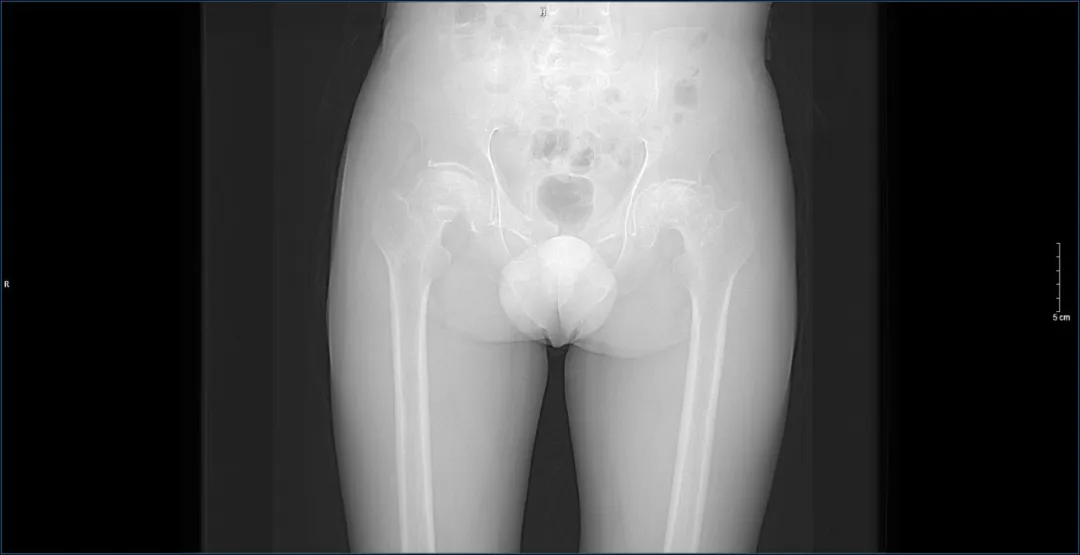

据了解,患者因长期饱受“双侧股骨头坏死”的折磨,生活受到了严重影响。在多方求医无果后,他们最终选择来到济南南郊医院,找到了杨学良主任团队。面对患者的复杂病情,杨学良主任没有丝毫犹豫,立即组织团队进行了深入的病例研讨。结合医学影像及一系列完善的检查,团队为患者量身定制了一套分阶段髋关节置换术的手术方案。

手术方案决定先为患者进行右侧髋关节置换手术,待术后恢复良好,再进行左侧髋节置换手术。这一决策不仅体现了杨学良主任团队的专业素养,更彰显了他们对患者生命的尊重和负责。手术过程中,杨学良主任凭借精湛的医术和丰富的经验,带领团队顺利完成了手术。术后,患者在医护人员的精心照料下,恢复迅速,经过复查,各项指标均符合预期手术目标,生活质量得到了极大改善。